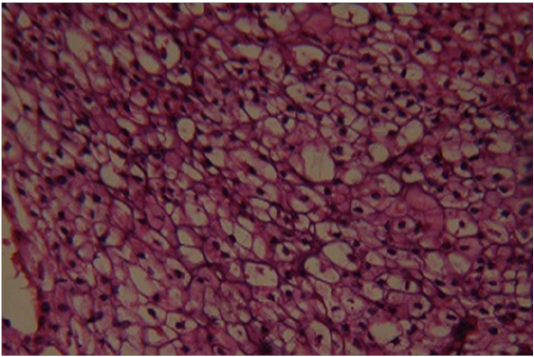

Figure 5

Sublingual lymphnodealso revealingpleomorphic chondrocytes (H&E×400)